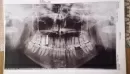

Была у стоматологов, делали рентген и нижних, и верхних зубов, они не нашли причину. Была у ЛОРа и невропатолога — тоже ничего.

Я уже измучилась, что со мной не так. Со слов врачей по снимкам все хорошо.

Прикрепленые фото

Дело в том, что пульповые камеры в нижних зубах у Вас узкие, как бы в стадии зарастания, как у людей в возрасте, а количество зубов во рту соответствует молодому возрасту.

Возможно причина в этом, потому что имплант установлен нормально и явных причин для указанных Вами симптомов на снимках не просматривается.